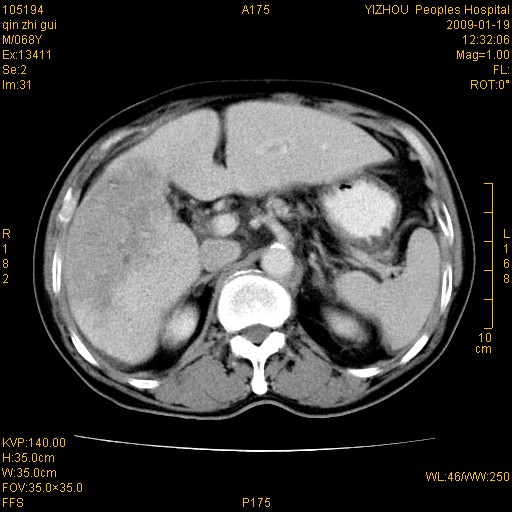

以下是引用随光逐影在2009-1-21 16:11:00的发言:[br]1)考虑肝右叶肝癌并肝静脉及门静脉瘤栓形成。2)肝硬化,少量腹水。3)胆囊炎。4)右侧少量胸腔积液。

病灶外缘凹凸不平,平扫低密度,增强动脉期有强化,门脉早显,静脉期及延期呈延迟强化,结合病史考虑右肝前叶巨块型肝癌可能性大,强化表现不除外胆管细胞癌